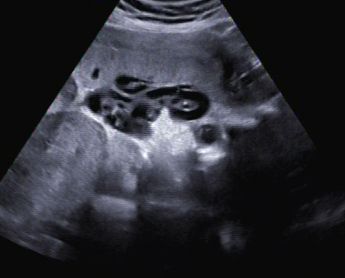

Ein zunächst durchgeführtes CTG war unauffällig. Im Rahmen der sonografischen Untersuchung zeigte sich der Fötus soweit beurteilbar zeitgerecht entwickelt. Dennoch konnte ein Anhydramnion festgestellt werden(Abb. 1, 2), weshalb auch kein fetales Gesicht darstellbar war (Abb. 3).